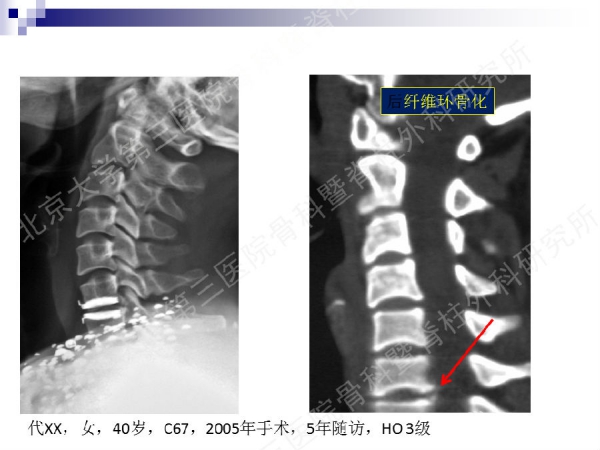

今天,在北京大学第三医院骨科暨脊柱外科研究所刘忠军教授分享的《颈椎人工椎间盘置换手术注意问题》课件中,他将通过大量影像资料、临床研究数据和长期随访结果,给大家介绍现阶段最重要的颈椎非融合技术——人工椎间盘置换术的适应证、禁忌证和其他需要密切注意的一些问题,提醒同道关注与手术技术及内植物相关的尺寸、终板顺列、中心轴线顺列等问题,严格把控手术指征,规范、精准地开展颈椎人工椎间盘置换手术,保障手术疗效。